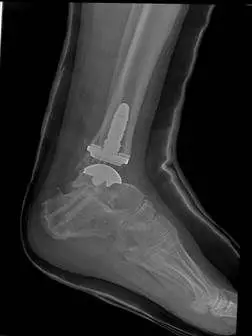

The following are images after surgical replacement of the ankle joint with a mobile bearing ankle prosthetic called the S.T.A.R. (SBI). This replacement joint will function similarly to a normal anatomical joint, allowing the patient normal function in daily activities, but was not designed to take repetitive use during more intense athletic activity. The joint has a polyethylene spacer between two metal parts that acts as shock absorber and gliding agent similar to cartilage. There is physical therapy that is required after surgical joint replacement in order to get the patient back to funcional capacity.

Post-traumatic arthrirtis treated with Total Ankle Replacement